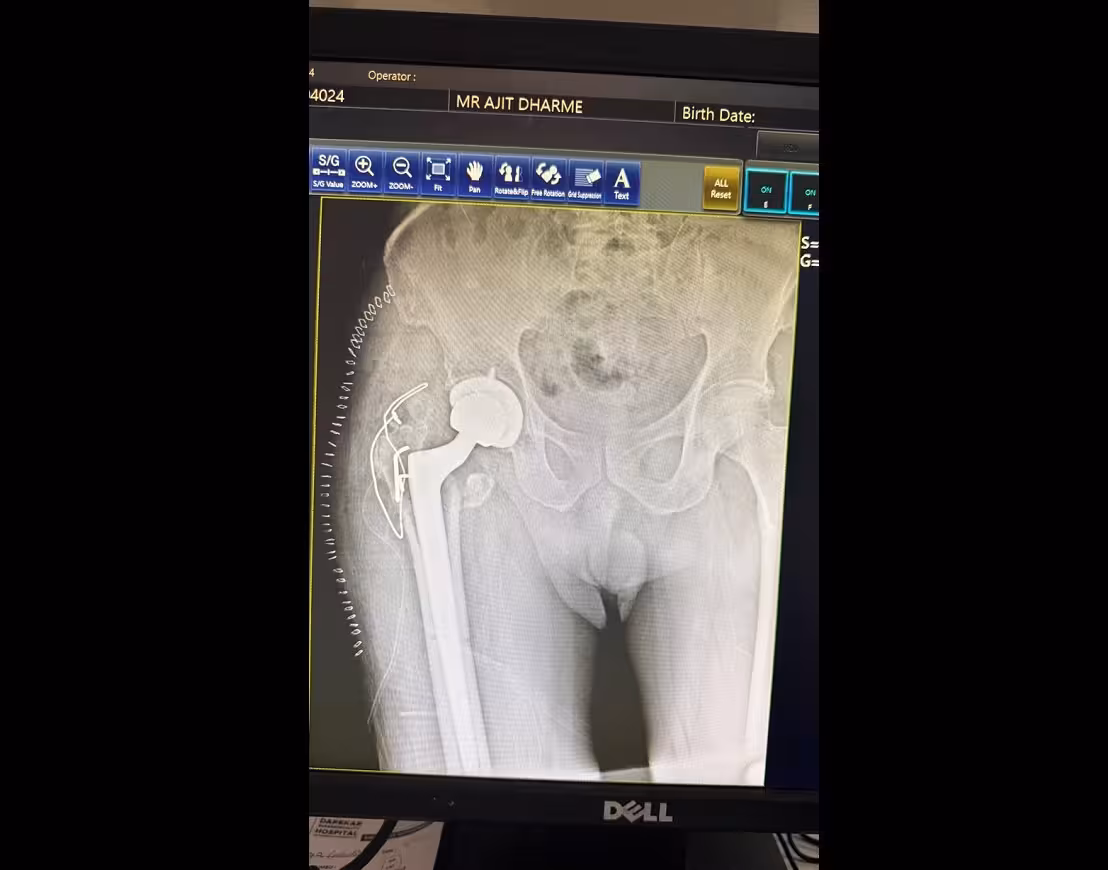

Robotic Partial Hip Replacement is an advanced orthopedic procedure designed to replace only the damaged portion of the hip joint while preserving healthy bone and tissue. Dr. Mangesh Darekar is a leading Robotic Joint Replacement Surgeon in Pune offering precision-based robotic partial hip replacement surgery.

This minimally invasive robotic-assisted procedure ensures accurate implant placement, improved joint stability, reduced pain, and faster recovery compared to conventional hip surgery.

In partial hip replacement (hemiarthroplasty), only the damaged femoral head is replaced while the natural hip socket (acetabulum) is preserved.